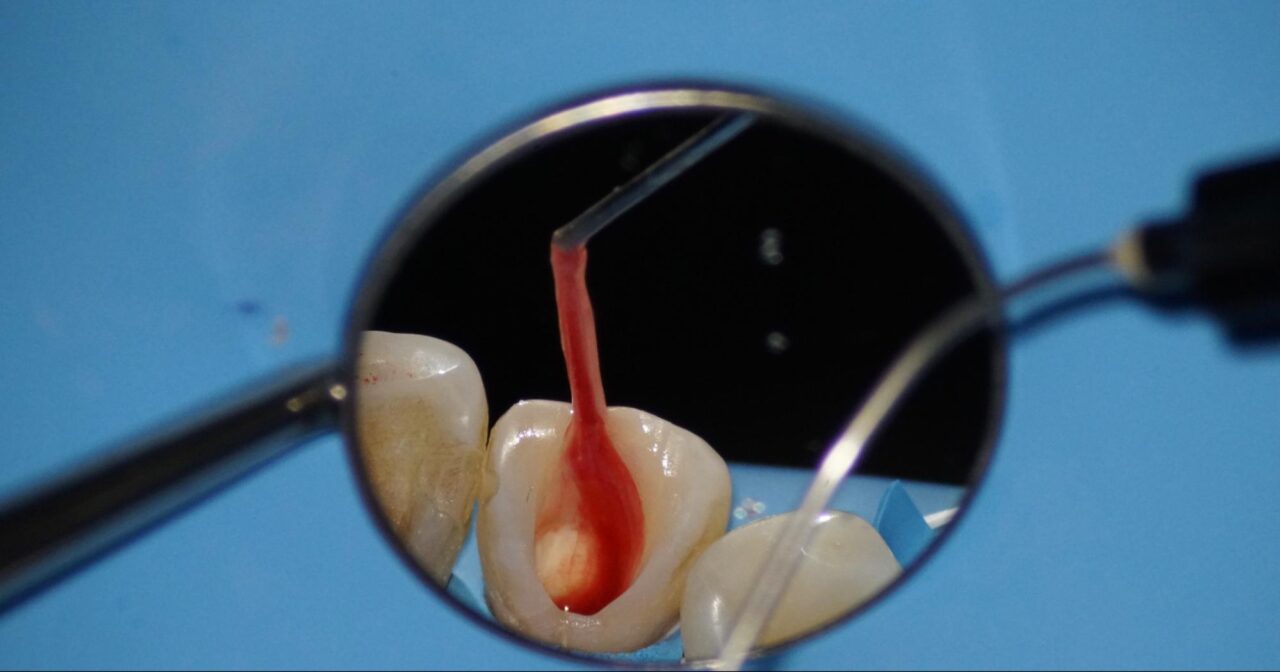

随腔内は健全な歯髄は確認できず、腐敗して溶けかかっているように観えます。

歯髄は、溶けかかっているため、マイクロバキュームで一部を吸い上げる事ができます。